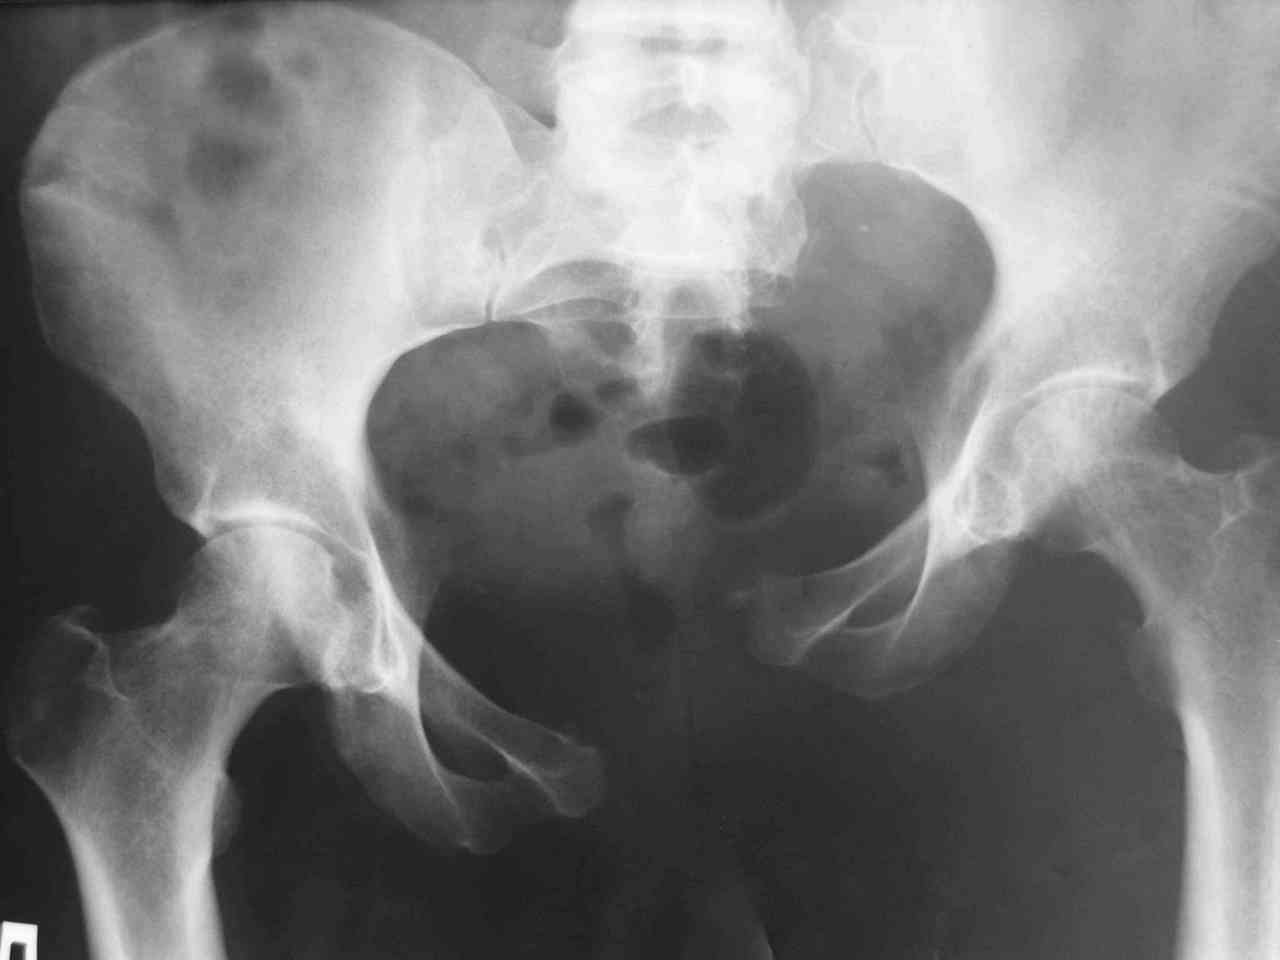

Пациентка получила травму таза 9 месяцев назад (перелом латеральной

массы крестца слева, разрыв лонного сочленения). Лечилась в стационаре

другого города, без успеха. В мае 2007 прооперирована в нашем

отделении, выполнена открытая репозиция повреждений, остеосинтез

винтами латеральной массы крестца и пластинами лонного сочленения.

Дополнительная  фиксация аппаратом внешней фиксации. 3 недели спустя

упала в палате на ягодицы, при этом получила повторную травму таза,

смещение отломков. Уважаемые коллеги каково ваше мнение о способе

фиксации полученных повреждений. С уважением Алексей.